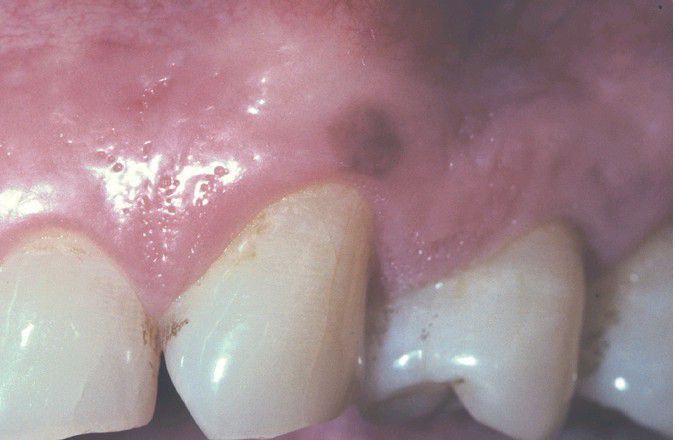

Oral Melanotic Macule

. A well-demarcated brown macule of the gingival mucosa.